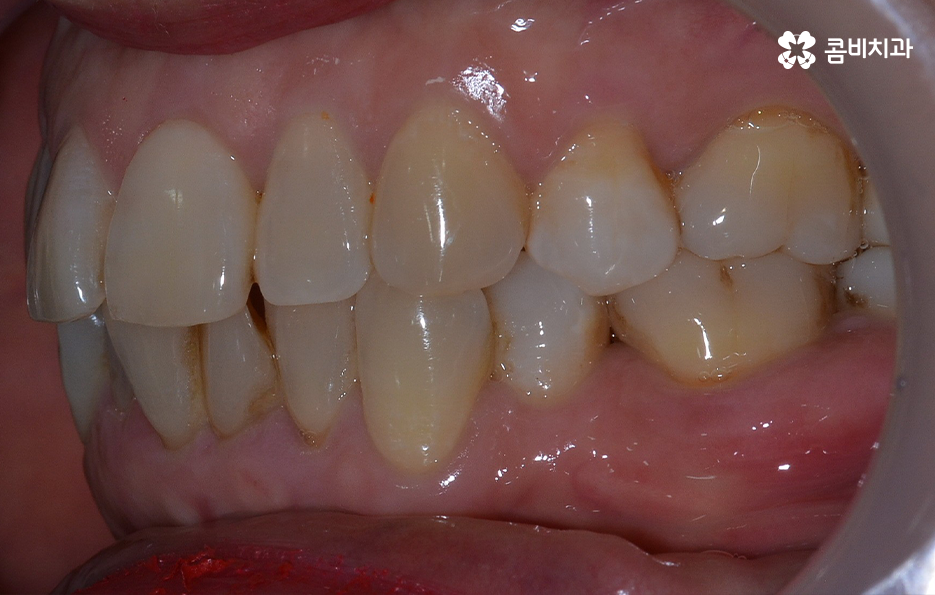

오늘 보시는 교정 사례의 경우를 보시면 아랫니의 틀어짐도 크지만 측면 사진으로 보시면 치열로 인해 돌출입에 영향을 준다는 사실도 알 수 있어요. 즉 치열과 함께 돌출입도 함께 고치고 싶어하기 때문에 치열도 재배열 하지만 치아 안쪽으로 넣어서 입술라인과 얼굴형으로 볼 때도 돌출입도 치료하는 치료 계획을 세웠기 때문에 작은 어금니 발치를 통한 치아의 이동 공간을 확보한 사례로 볼 수 있어요

치아교정의 원리를 생각하면 치아를 안쪽으로 넣어야 하는 치료 계획을 세울 때 치아가 이동할 수 있는 공간을 확보해야 하고 특히 얼굴형까지 고려하여 치아를 크게 이동시켜야 할 때는 발치 교정이 꼭 필요할 수 있는데요